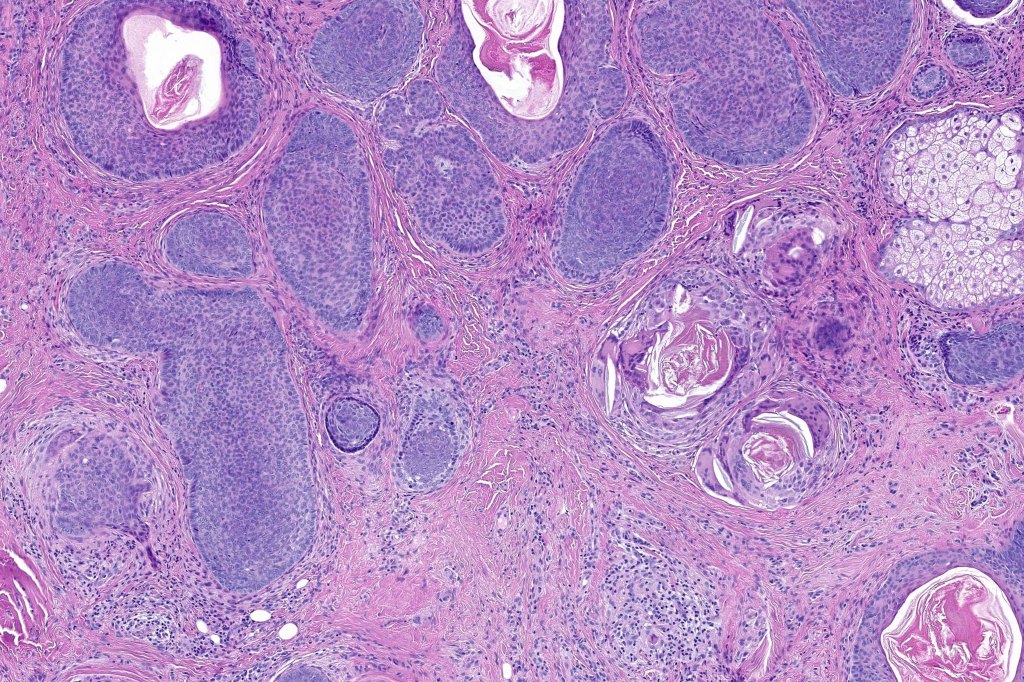

•Trichogerminoma (see images)

•Most common tumor arising in nevus